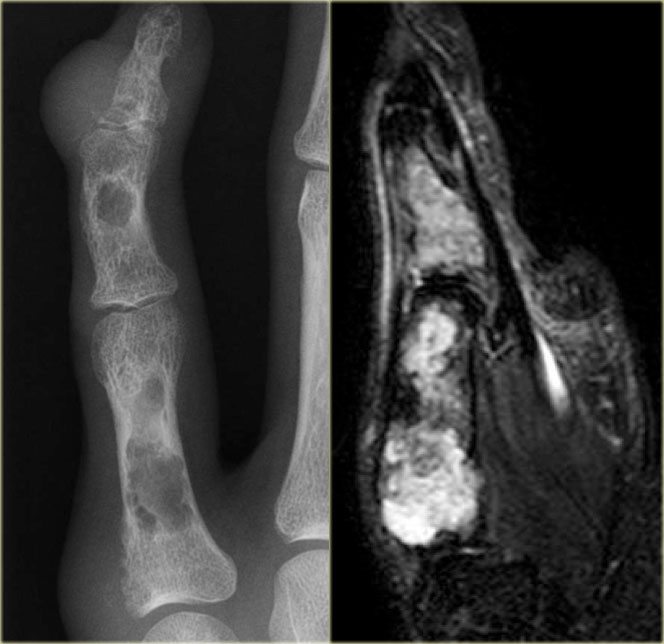

ABC (4)

On the left images of an aneurysmal or expansile well-defined osteolytic bone lesion in the proximal phalanx.

Notice the expansion and the enhancing rim.